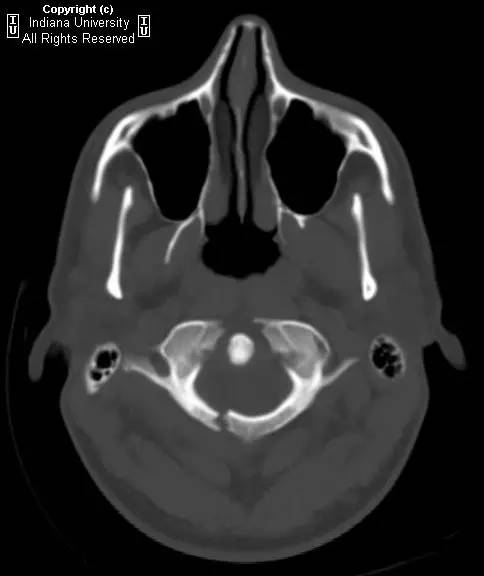

CR: C1侧块相对C2侧块外侧移位约5 – 6 mm,符合Jefferson骨折。椎体周围软组织明显肿胀。MR: 椎体周围间隙可见血肿。覆膜完整。寰枕前韧带断裂。寰枢前韧带完整。左侧横韧带从C1侧块的内侧分离,CT对应在C1侧块内侧见小撕脱骨折。翼状韧带完整。寰枕后韧带完整。前纵韧带和后纵韧带完整。黄韧带完整。

Jefferson骨折(Jefferson fracture)是前后弓均累及的C1环粉碎性骨折。Jefferson骨折为头顶受打击并轴向载荷的结果,力从颅骨经枕骨髁传递到颈椎,C1侧块在枕骨髁和C2上关节面之间被压缩,基于侧块的形状产生向心力而导致C1爆裂骨折。齿状突开口位或冠状位重建CT图像应仔细观察双侧C1和C2关节侧块间有无偏移。虽然C1侧块相对C2上关节面侧方移位提示存在骨折,但在X线片上有时难以发现骨折线。MR可显示相应的韧带损伤。

Jefferson骨折。A,侧位片示C1后弓骨折线(箭)。B,开口位示C1侧块相对于C2偏移(箭)。C和D,轴位CT图像示骨折线通过C1环前、后部(箭)。E,冠状位CT图像示翼状韧带小的撕脱骨折(黑箭)。此图像上也标注了C1在C2上方偏移(白箭)。